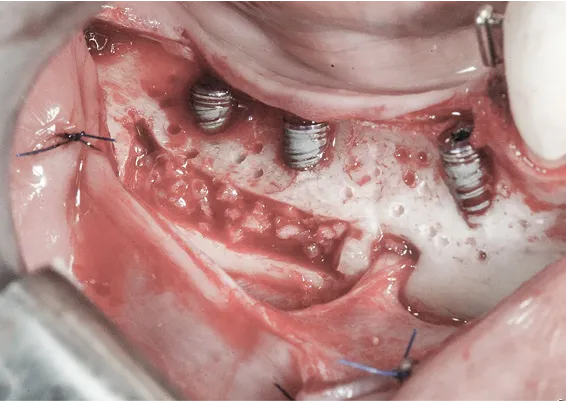

ZABIEGI REGENERACJI KOSTNEJ WOKÓŁ WSZCZEPIANYCH IMPLANTÓW

Sterowana regeneracja kości GBR przy użyciu biomateriałów oraz membran zaporowych. Procedury te są stosowane w sytuacji niedostatecznej ilości kości, skutkującej odsłonięciem gwintu, podczas gdy wszczepiamy implanty stomatolo-giczne lub też jako zabiegi poprzedzające ich wprowadzenie.

TRÓJWYMIAROWA REKONSTRUKCJA WYROSTKA ZĘBODOŁOWEGO PRZY UŻYCIU INDYWIDUALNIE DRUKOWANYCH SIATEK TYTANOWYCH YXOSS ReOss

To kolejna metoda umożliwiająca precyzyjną odbudowę zadanego kształtu tkanki kostnej przy użyciu standardowych materiałów kościotwórczych, kości własnej lub PRF oraz zewnętrznego rusztowania w postaci siatki z biozgodnego stopu tytanu. Siatka jest indywidualnie projektowana w technologii CAD CAM i następnie drukowana dla konkretnego przypadku.

Dotychczas stosowane stabilizatory zewnętrzne w formie siatek tytanowych używane do regeneracji kostnej lub w zabiegach odtwórczych w chirurgii szczękowo-twarzowej uwzględniały materiały ręcznie doginane i formowane podczas zabiegu operacyjnego. Zastosowanie technologii CAD CAM dla potrzeb druku materiałów przeznaczonych do indywidualnej rekonstrukcji kostnej znacznie poprawiło precyzję i jakość uzyskiwanych efektów. Wdrożenie biozgodnych stopów tytanu do druku siatek zdecydowanie ograniczyło odsetek powikłań zapalnych.

Precyzja projektu druku siatki bazuje na dokładności odwzorowania kształtu kości w stożkowej tomografii komputerowej CBCT, co zapewnia ich dobre przyleganie do podłoża kostnego oraz ogranicza powstawanie powikłań w postaci obnażania się siatek. Precyzja projektu oraz materiał, z którego wykonana jest siatka (biozgodny stop tytanu), powodują, że obnażenie się siatki nie zaburza procesu gojenia i regeneracji kostnej.

Wymaga jedynie większej ilości kontroli pozabiegowych oraz wzmaga czujność higieniczną zarówno ze strony lekarza, jak i pacjenta. Ten rodzaj odbudowy kostnej stosowany jest w sytuacjach złożonych, trójwymiarowych 3D ubytków kości, przy których standardowe metody odbudowy są niewystarczające. Ilość kości, którą możemy uzyskać, stosując tę metodę, to nawet kilka centymetrów sześciennych.

Metoda rekonstrukcji kostnej w oparciu o indywidualnie drukowane siatki z tytanu dla implantacji wszczepów śródkostnych stosowana jest najczęściej jako dwuetapowa. W pierwszym etapie odbudowywana jest kość, natomiast implanty wszczepiane są po okresie 4–6 miesięcy. Na wgojenie implantów oczekujemy od 4 do 6 miesięcy w zależności od miejsca ich lokalizacji. Siatka tytanowa po spełnieniu swojej funkcji rusztowania dla odbudowującej się kości jest następnie usuwana w dniu wszczepienia implantu. Jeżeli kość spełnia odpowiednie warunki, istnieje możliwość zastosowania modyfikacji siatki tytanowej, która umożliwia jednoczesne wprowadzenie implantów wraz z odbudową kostną.